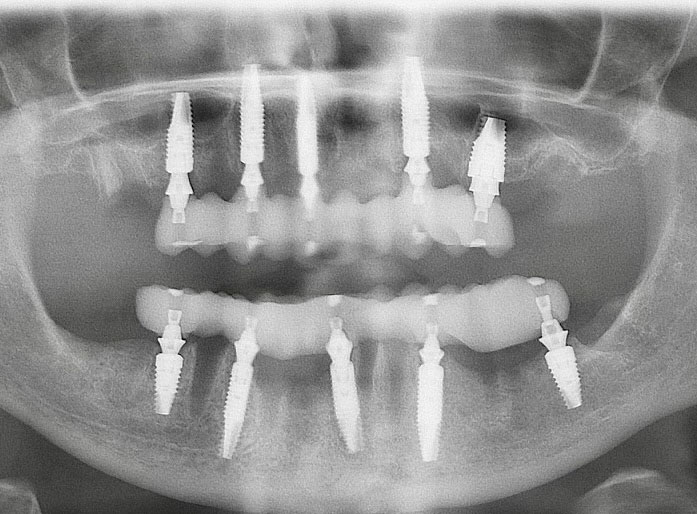

Fig 21. Postoperative panoramic radiograph on the day of surgery.

Figure 21

Fig 6. Postoperative panoramic radiograph on the day of surgery.

Figure 6

Fig 40. Postoperative panoramic radiograph on the day of surgery.

Figure 40